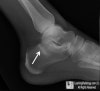

X-ray : Normal calcaneus(Lateral view)

X-ray : 종골 골절(Calcaneal fracture) - Lateral view

1. Flattening of Bohler's angle

2. Depression of the articular surface of the posterior subtalar joint (red line)

from its normal position (green line)

3. Fracture lines can be seen passing through the calcaneus